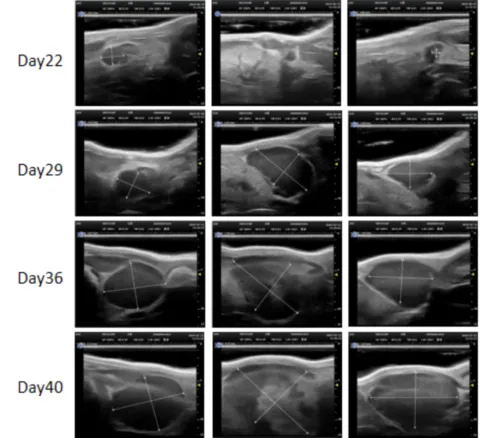

PDX Model (Growth Curve)

部分HJC黄金城平台PDX原位模型展示